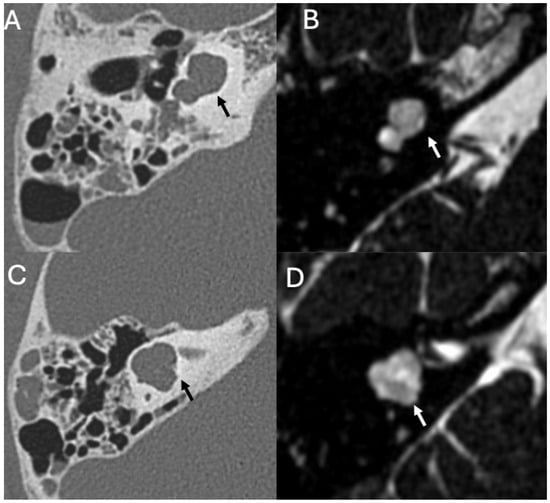

3.1. Otomastoiditis

3.1.1. Imaging

| Otomastoiditis and Otogenic Meningitis | Saat et al., 2015 [17]; Rubini et al., 2024 [18]; Vazquez et al., 2003 [19]; Bruschini et al., 2017 [20]; Barry et al., 2019 [21] | Retrospective studies, imaging reviews, and case reports | HRCT and MRI identify middle ear/mastoid infection and intracranial spread; meningitis occurs in up to 35–46% of untreated cases. |